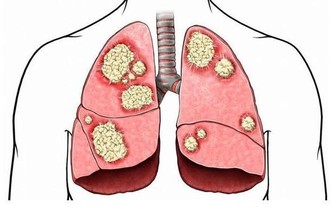

演變成肝癌的過程,是有著一個三部曲,那就是肝炎、肝硬化、肝癌的這樣子一個過程。其中,引起肝癌的誘因還有黃曲霉毒素,由於特別容易被忽視,尤其是在廚房裡面,那就需要特別引起人們的注意。